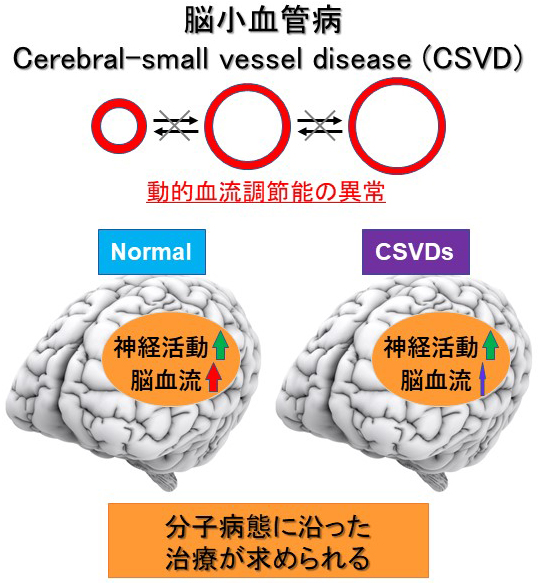

カラー ルービン病理学: 臨床医学への基盤 | ラファエル。新品未使用】カラー ルービン病理学 臨床医学への基盤 改訂版。カラー ルービン病理学: 臨床医学への基盤 | ラファエル。p*す様 ミルキークイーン ☆ 玄米 ☆ 10kg。カラー ルービン病理学: 臨床医学への基盤 | ラファエル。病理学 - 西村書店。朝倉書店『内科学』(第12版)デジタル付録。「カラー ルービン病理学 臨床医学への基盤」鈴木 利光 / 中村 栄男 / エマニュエル・ルービン定価: ¥ 11000#鈴木利光 #鈴木_利光 #中村栄男 #中村_栄男 #エマニュエル・ルービン #本 #自然/医療・薬学・健康。ルービンカラー基本病理学 第5版 | エマニュエル ルービン。カラー ルービン病理学: 臨床医学への基盤 | ラファエル。ルービン カラー 調和のとれた 基本病理学 中古本。国内初、先天性中枢性低換気症候群に対する横隔膜ペーシング治療。脳血管の分子病態研究 | 研究紹介 - 新潟大学脳研究所 脳神経内科。日本がん対策図鑑 | 【標準治療】EGFR陽性肺がん